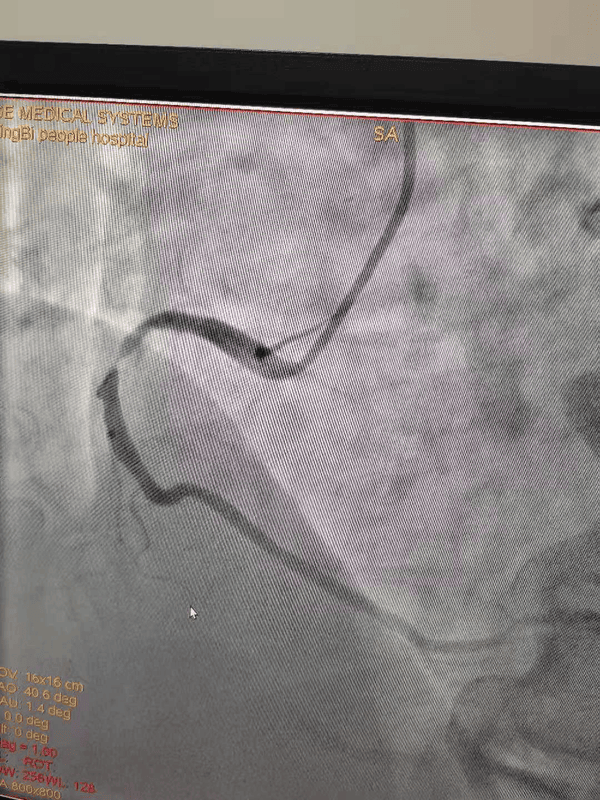

支架植入后

65岁的魏大爷因反复胸闷、胸痛入住我院心内一科,完善检查后被诊断为冠心病、心绞痛。经充分准备,予以冠脉造影+支架植入术。这是我院第一例700元左右支架手术,手术进展顺利,术中支架通过性、可塑造性、安全性均表现良好。魏大爷也幸运的成为我院第一个享受国家优惠政策的冠心病患者。